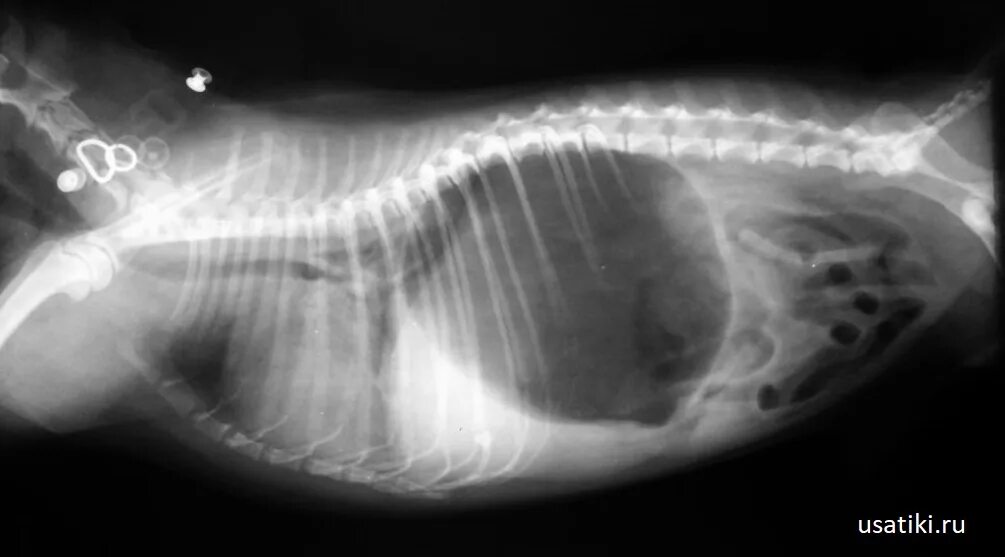

Лимфома у собак симптомы